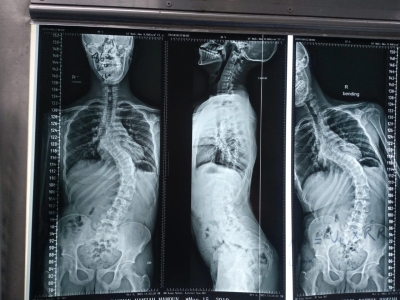

خبرني - شهد قسم جراحة العمود الفقري في مستشفى الأمير حمزة إنجازًا طبيًا مميزًا تمثّل في إجراء تدخّل جراحي معقّد لتصحيح جنف العمود الفقري لدى أحد المرضى الذين يعانون من تشوّه حاد في الفقرات.

وقد أُجريت العملية باستخدام جهاز الملاحة الجراحية المتقدّم، الذي أتاح دقةً عالية في التعامل مع التشوّهات البنيوية الشديدة، وسهّل توجيه الأدوات الجراحية ضمن المسار الآمن والمثالي.

كما اشتملت العملية على إزالة أجزاء محددة من الأطراف الخلفية للفقرات لتحقيق التصحيح المطلوب واستعادة التوازن والمحاذاة الطبيعية للعمود الفقري.